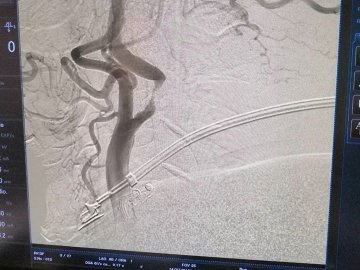

Зазначаєтся, що 53-річний пацієнт звернувся за медичною допомогою зі скаргою на часті втрати свідомості.

І вже після додаткових обстежень лікарі виявили, що просвіт обох внутрішніх сонних артерій був значно звужений – більше зліва до 95%.

Тож хірурги Ковельського МТМО успішно провели стентування (внутрішньої сонної артерії) зліва. Стент, який був використаний для проведення операції, відновив звичний діаметр судини та відповідно кров у більшому об'ємі почала надходити до головного мозку.

Тож стан пацієнта значно покращився. Проте його чекає ще одна операція.